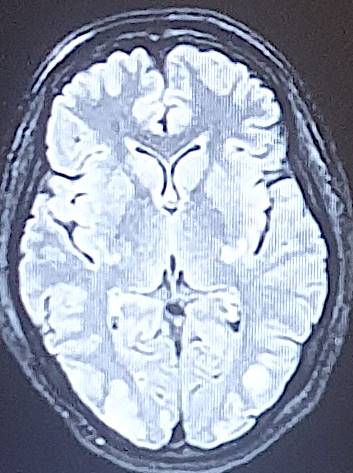

The average consultation time was 24.3 ± 14.4 hours, with extremes of 7 hours and 44 hours. Clinical presentations were headache (88.2%), visual disturbance (64.7%), disturbed consciousness (35.3%), epileptic seizures (23.5%) and motor deficit (29.4%) (Table 2). Mean systolic blood pressure was 190 ± 5.7 mmHg (extremes 150 - 24 mmHg), mean diastolic blood pressure 110 ± 5.1 mmHg (extremes 80 - 160 mmHg). Neuroradiological lesions (Figure 1) were edematous (88.2%), hemorrhagic (23.5%) and ischemic (11.7%). The topography of cerebral lesions was occipital (100%), parietal (82.3%), frontal (58.8%), temporal (47%), cerebellar (29.4%) and basal ganglia (23.5%) (Table 3).

Figure 1. Breakdown of cases by neuroradiological lesions.

Our findings on lesion topography (Figure 2 and Figure 3) are similar to those in the literature, which report that the parieto-occipital, frontal and temporal regions are most involved. More rarely, lesions may extend to the basal ganglia (14%), brain stem (13%) and splenium of the corpus callosum (10%) (Leroux et al., 2008). A normal CT scan does not exclude the diagnosis of PRES (Poma et al., 2014). Intracerebral hemorrhage is observed in 5% - 30% of PRES cases (Aracki-Trenkić et al., 2016; McKinney et al., 2012).

Figure 2. Bilateral occipital vasogenic edema.

Figure 3. Bilateral frontal-parietal-occipital edema with left lenticular hemorrhage.